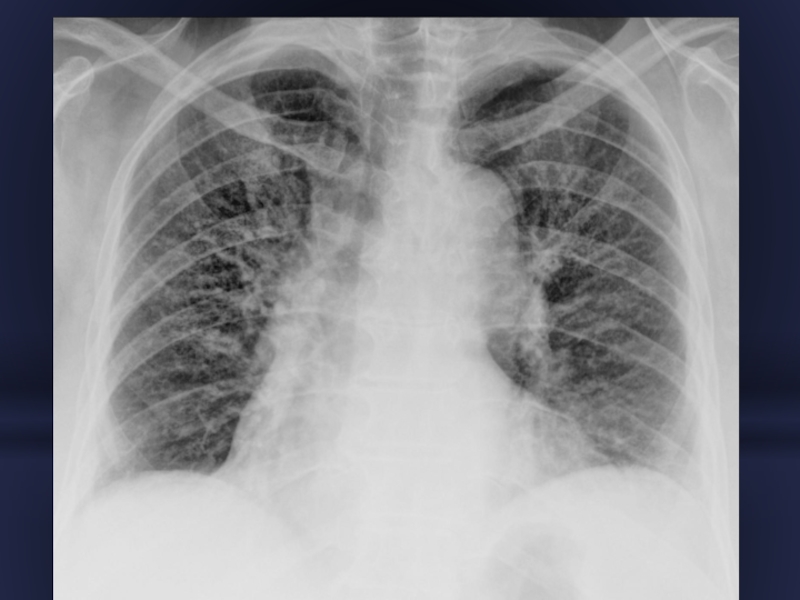

Слайд 33ТОТАЛЬНЕ ЗАТЕМНЕННЯ -

протяжність 3 легеневих поля

Причини часті: ателектаз, рідина в плевральній

порожнині, пневмонія, фіброторакс.

СУБТОТАЛЬНЕ ЗАТЕМНЕННЯ - протяжність 1 легеневе поле

Причини ті ж + набряк, цироз, невелика пухлина.

Слайд 38Ексудативний плеврит тотальне затемнення